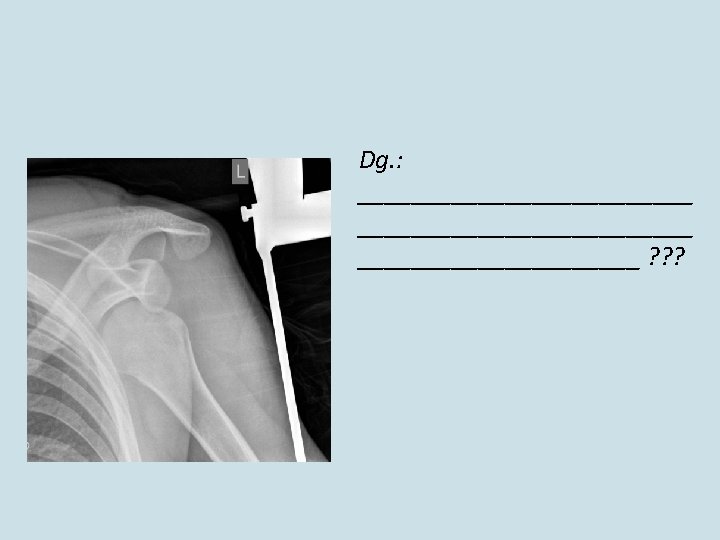

vulnus ____ regionis _____ vulnera _____________ ? ?